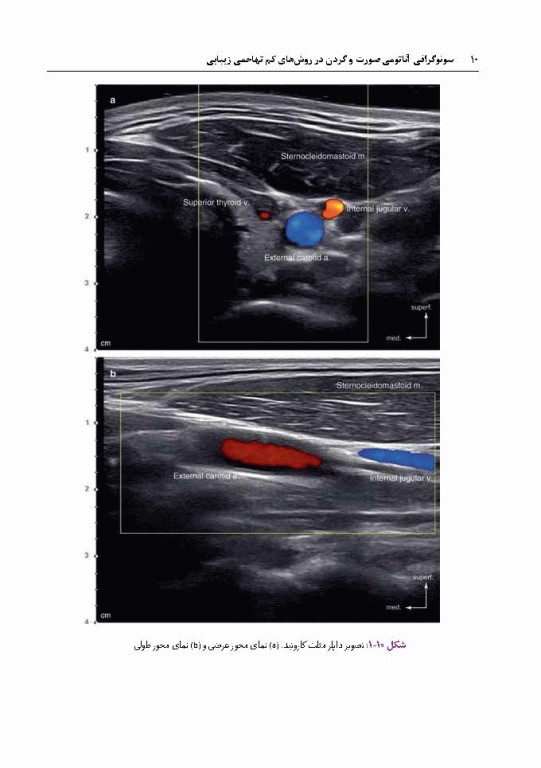

سونوگرافی آناتومی صورت و گردن در روش‌های کم تهاجمی زیبایی

کتاب سونوگرافی آناتومی صورت و گردن در روش‌های کم تهاجمی زیبایی ترجمه دکتر رضا صادقی و سعیده صفایی توسط انتشارات آبادیس طب به چاپ رسیده است. سونوگرافی به پزشکان این امکان را می‌دهد تا با هدف قراردادن دقیق عضله برای رسیدن به نتایج مطلوب از حداقل مقدار توکسین بوتولینوم استفاده کنند. علاوه بر این، سونوگرافی به فرد این امکان را می‌دهد تا در حین تزریق فیلر و پروسیجر لیفت با نخ برای به حداقل رساندن عوارض مختلف، لایه دقیق را پیدا کند.

تکنیک‌های رایج بدون استفاده از سونوگرافی ممکن است باعث عوارض عروقی مانند خونریزی، هماتوم، کبودی و آتروفی پوست شود. بر اساس این پیشینه این کتاب شامل 10 فصل با 537 تصاویر ترسیم شده و سونوگرافی است که در فصل های 1 و 2 با عنوان اصول اولیه سونوگرافی و آناتومی کلی بیان شده و فصل‌های 3 تا 7 بر اساس آناتومی بالینی صورت و گردن، تفسیر تصاویر سونوگرافی هر قسمت را شرح می‌دهد. 3 فصل آخر کتاب شامل تکنیک‌های جدید پروسیجر‌های تحت هدایت سونوگرافی در توکسین بوتولینوم، تزریق فیلر و قراردادن نخ به صورت ایمن تشریح و نشان داده شده است.